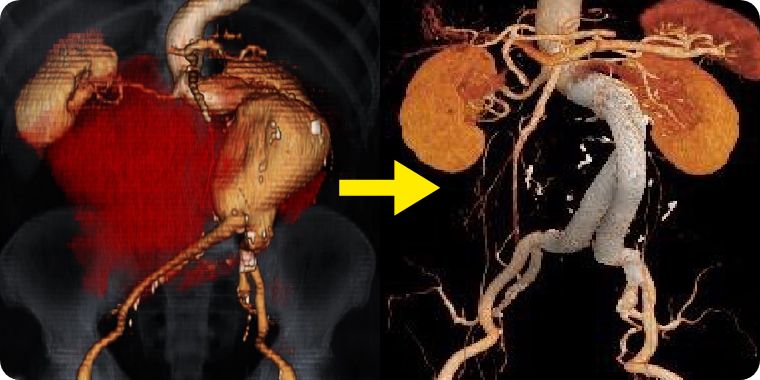

併存疾患や年齢により人工血管置換術に耐えれない方に向けて、体への負担が少ない治療が開発されました。

足の付け根の血管から、カテーテルを使用して人工血管(ステントグラフト)を大動脈に挿入し、大動脈瘤破裂を防ぐ治療になります。

当院では皮膚を切開しないで行うステントグラフト治療を積極的に施行しております。他施設に先駆けて2013年から皮膚を切開しないでステントグラフト治療を行い、胸部大動脈瘤でも導入しております。導入から500例を超える症例に皮膚を切開しないステントグラフト治療を行いましたが、入院日数は平均3-6日です。局所麻酔で行うため、全身麻酔が困難といわれた方に対しても安全に治療をしています。

腹部大動脈瘤破裂に対して施行した緊急ステントグラフト内挿術